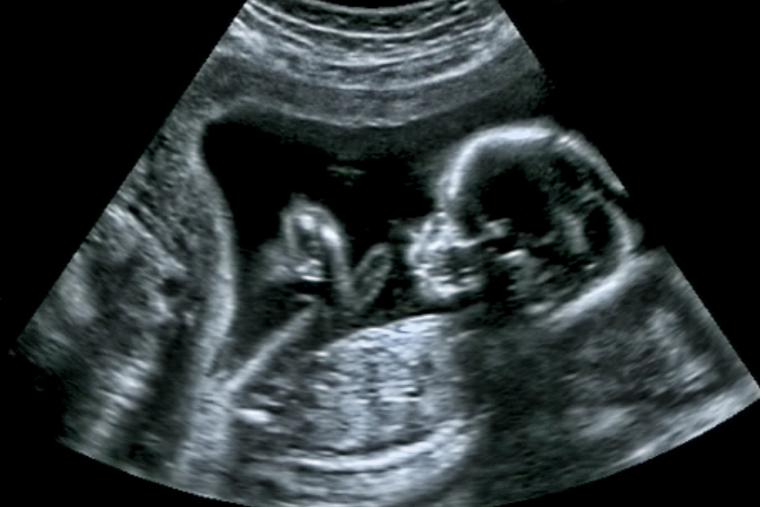

Rather, some infants with genetic or congenital abnormalities who might otherwise have been aborted are now being born and passing away, said Dr. Ingrid Skop, an obstetrician and the vice president and director of medical affairs at the Charlotte Lozier Institute.

In many cases, children with genetic abnormalities are now being brought to birth and then dying from those abnormalities after birth, she said.

“These are children whose abnormalities are significant enough that they would have died at some point,” she said, “but rather than killing them before birth, they’re being born and then dying after birth, when they begin to be counted in our statistics.”